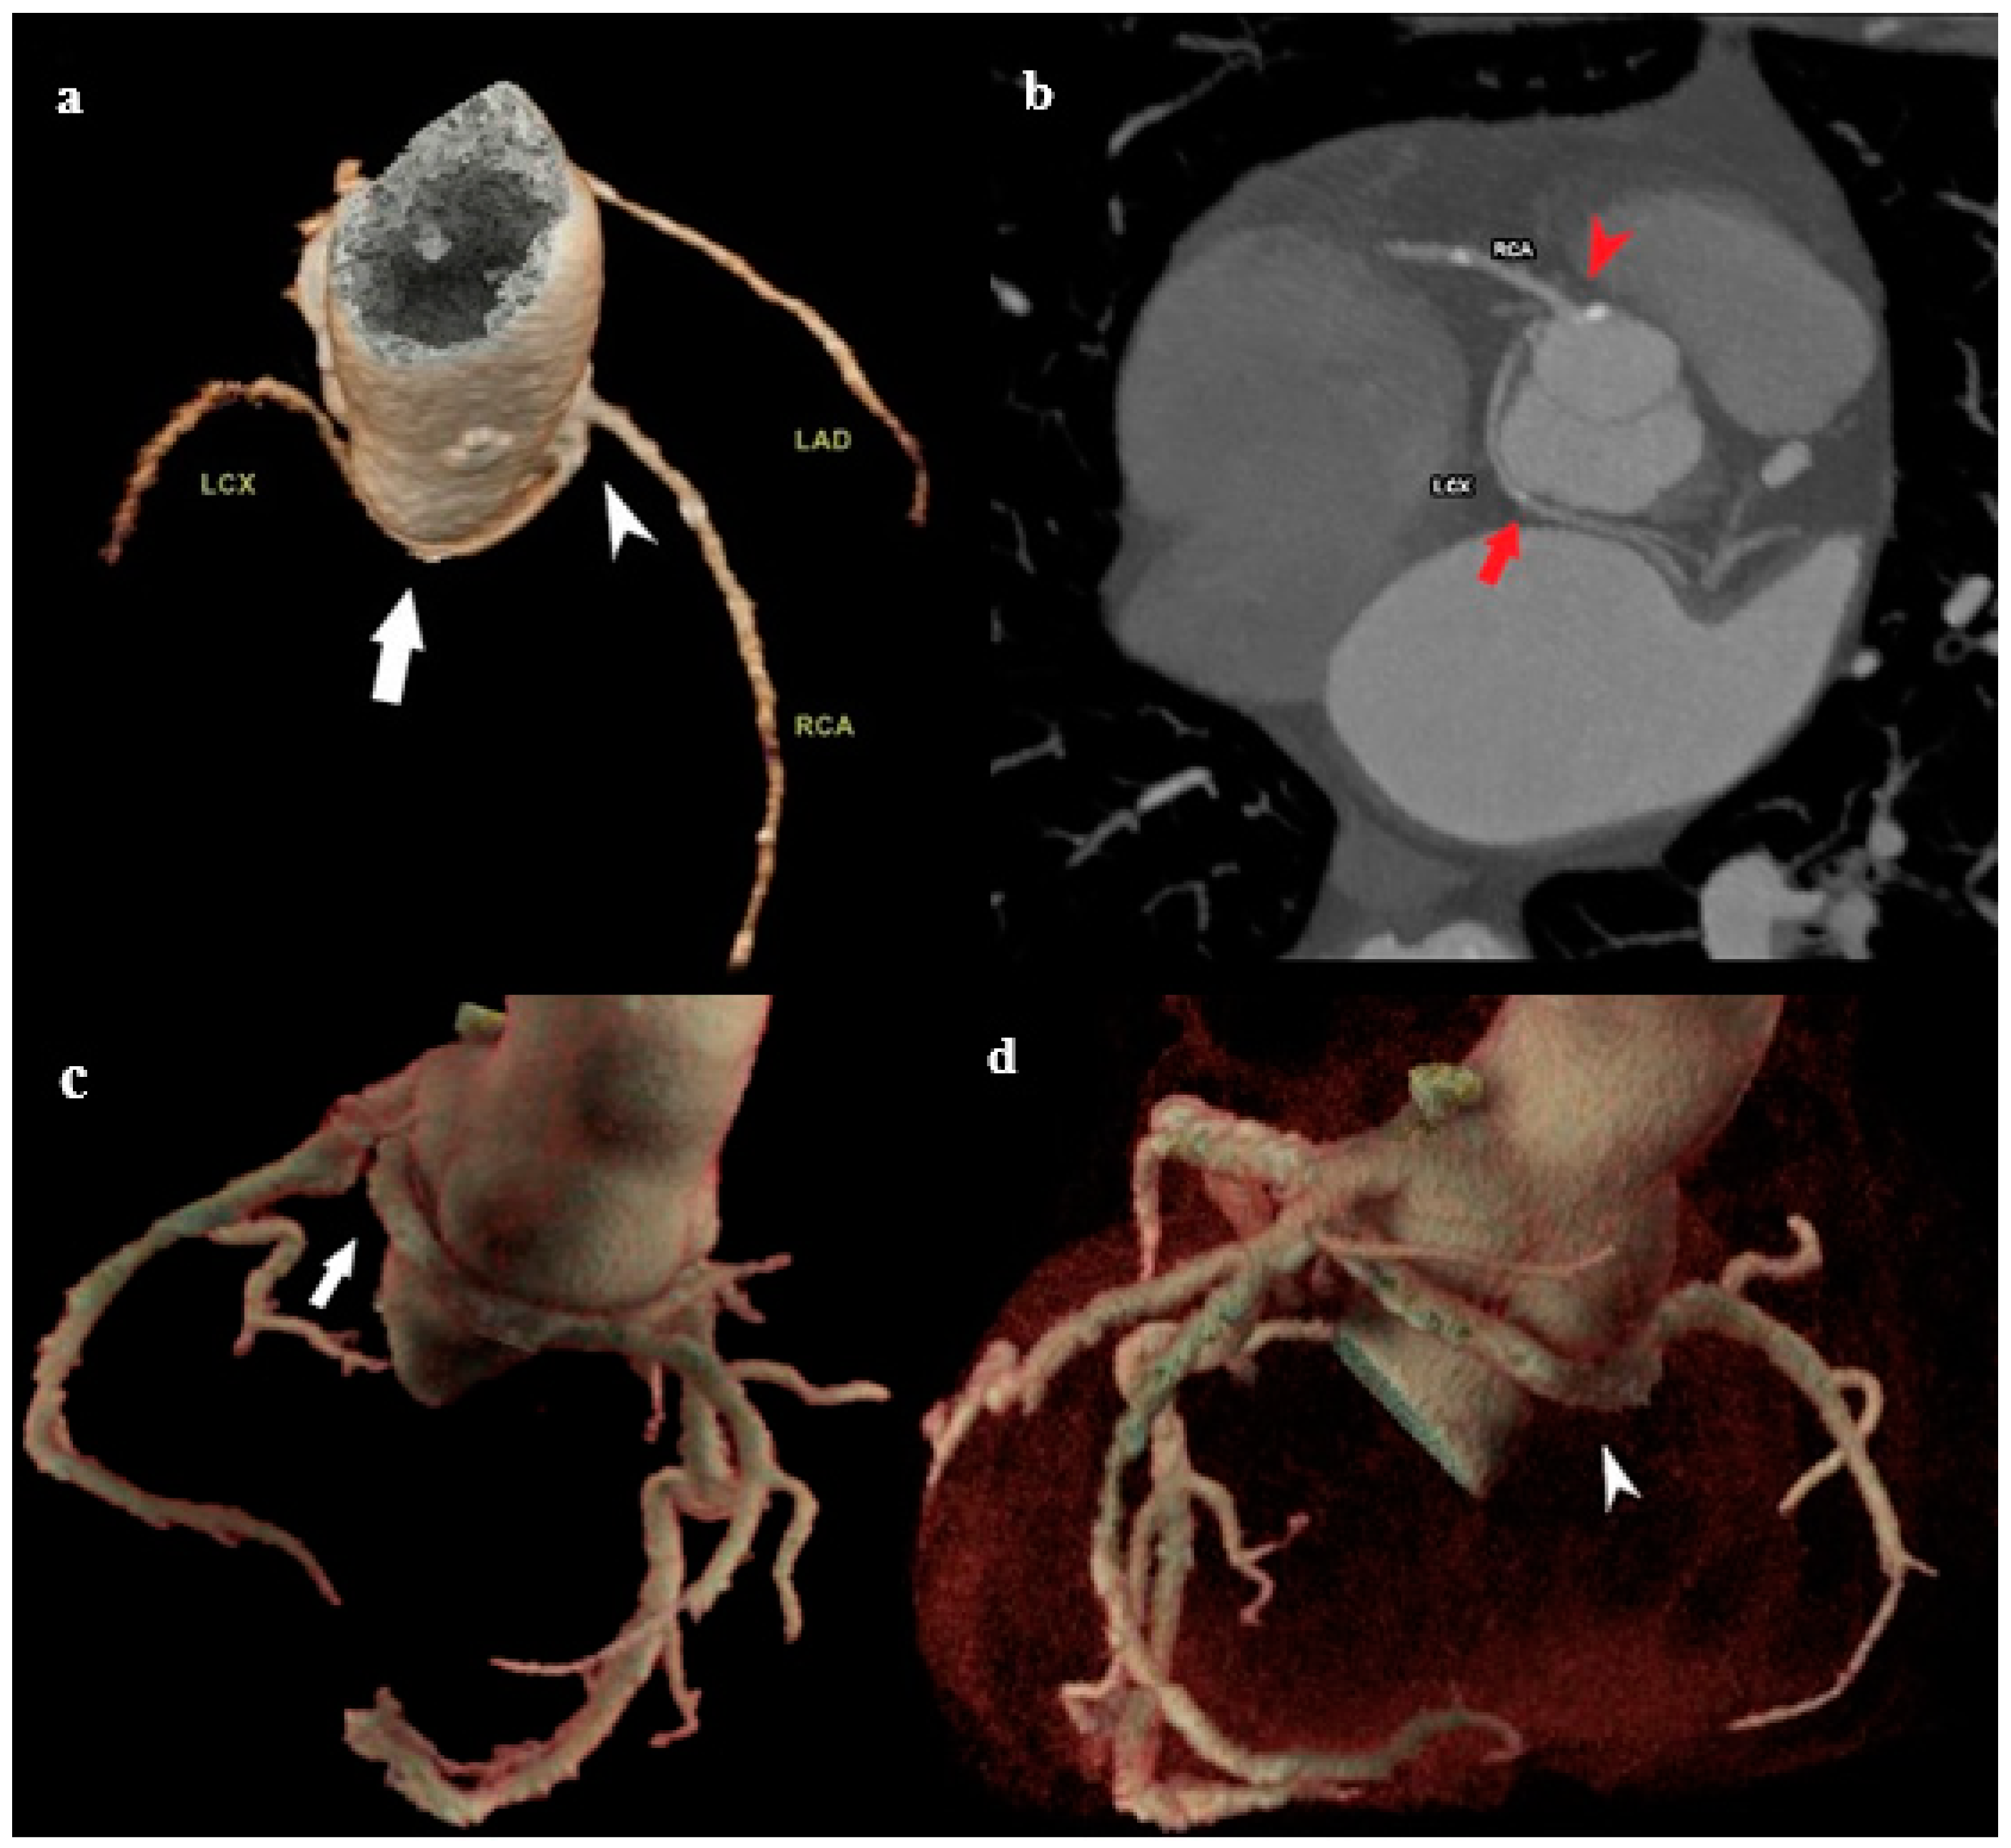

3.2.1. Left Main Artery (LMA) Trifurcation and Quadfurcation

The left coronary artery (LCA) typically originates from the left coronary sinus and left main coronary artery (LMA). It is smaller, measuring 5 to 10 mm long, bifurcating into the left anterior descending (LAD) and circumflexing (LCX) arteries [31]. The most common variation in the LMA anatomy is its third branch, the ramus intermedius artery, also called LMA trifurcation (Figure 6a), or less commonly, the fourth, obtuse marginal branch (OM), an LMA quadfurcation (Figure 6b) [32]. The ramus intermedius has variable branching and may extend diagonally, following the course of the LAD, or as a marginal branch, following the course of the LCX, depending on whether it supplies the anterior or lateral wall [33]. The peculiarity of this vessel is that it does not move along the anatomical groove but slides along the free surface of the left ventricle [34].

Based on different studies, the prevalence of this anomaly ranges from 12% [35] to 30% [36] in the general population and is typically asymptomatic. The predilection site for the onset of atherosclerotic disease is commonly observed at a wider angle of the LMA branching (trifurcation or quadfurcation) [9]. This observation is of significant clinical importance because of the previously mentioned rather high frequency of this anomaly. LMA trifurcation stenosis is a challenging lesion subset for percutaneous coronary intervention with its intrinsic anatomical complexity (three branches, at least four angles, wide variability in branch size, and disease) [37,38,39]. Therefore, the preprocedural evaluation of MDCT is crucial when planning coronary catheterization.

3.2.2. Double Right Coronary Artery (RCA)

A double right coronary artery is defined as two right coronary arteries of similar diameters and flows arising from one or two separate openings in the right sinus of Valsalva (Figure 7), generally having complete regular branches that occur in single RCAs, each of which has its posterior descending artery (PDA) in its distal course [40]. Double RCA is an extremely rare coronary anomaly, with a prevalence ranging from 0.07 to 0.46%, depending on the report [41,42]. This variation is primarily benign and is discovered incidentally during radiological diagnosis in patients with cardiorespiratory symptoms. However, it is a predilection site for atherosclerosis, life-threatening arrhythmias, and myocardial infarction. In addition, it sometimes presents challenges to performing interventional coronary procedures [43]. The exact diagnosis of a double RCA cannot be readily established based on conventional coronary angiography, because it is difficult to distinguish this variation from the variation in the high branching of the right coronary artery. For this purpose, MDCT coronary angiography is the method of choice to differentiate between these aberrations.

Figure 6. (a) MDCT coronary angiography showing trifurcation of LMA into LAD, LCX, and ramus intermedius (white arrow). (b) MDCT coronary angiography showing quadrifurcation with ramus intermedius (white arrow) and obtuse marginal branch (white arrow head). Understanding these variants is essential during revascularization procedures or coronary artery bypass grafting (CABG) to ensure all branches are adequately treated.

Figure 7. Double RCA. (a) MDCT coronary angiography revealed two separate RCAs originating from a single ostium in the right sinus of Valsalva (arrow). Both RCAs gave off branches with typical courses and in parallel distribution. (b) Planar view of two separate RCAs originating from a single ostium in the right sinus of Valsalva (black arrow head). Though usually benign, this variation must be clearly identified to avoid misinterpretation during angiography and to guide stent placement or surgery.